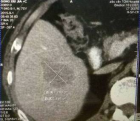

社会快速发展所带来的环境影响,让肿瘤离我们越来越近,当身边的人患有这种疾病时,给患者和亲人带来沉重的思想包袱,而开刀、化疗、放疗等传统治疗方式又给肉体带来更加痛苦的深层次打击。 患者往往对传统治疗望而却步,在绝望中等待生命的终结…… 问 还有希望吗!还有别的治疗方法吗? 答 有!而且还很易于接受。 一根细针,一根细细的PVC导管,或许就能给你带来希望。 通过细针,经皮穿刺病灶,取得细胞学、组织学等资料,可以让我们了解到底是恶性肿瘤还是良性疾病,并知道是什么类型的肿瘤;通过细针,可以让针尖加热,把肿瘤加热失去活性,就像把鸡蛋煮熟了再也孵不出小鸡那样,肿瘤就不再生长,而逐渐吸收变小;通过细针,可以把小小的粒子植入肿瘤,通过粒子缓慢释放能量,把肿瘤灭活,达到治愈肿瘤病灶的目的。 通过导管,进行血管造影进一步确认到底是不是恶性肿瘤;通过导管,并可把载有抗肿瘤药物微球直接注射进入肿瘤血管,缓慢持续长时间杀灭肿瘤细胞;通过导管,可以把给肿瘤供血的血管堵起来,让肿瘤失去血流,失去养料供给,饿死它。 上帝为你关上一扇门的同时,必定会为你打开了另一扇窗,快速发展的社会,科技日新月异,新技术新方法也给肿瘤治疗带来了新的希望。 近年来,淄博市中医医院介入科引入诸多新时代发展带来的前沿新技术,结合数千年古老神秘的中医调理,给诸多患者带来了新的希望和愉快的新生活。 病例一 2015.9 2015.9.11微波消融后 2017.4 肝动脉栓塞并粒子植入,病变直径75mm 2021.4.复查,病变直径35x23mm 病例二 2015.7 肝动脉栓塞并肝癌微波消融 2017.8 MRI复查,病变未见进展 2021.7 CT复查病灶显著缩小 患者后期按时复查,其他处有新增病灶,通过多次介入治疗,至今健在。 介入放射学 是在现代影像学(DSA、CT、超声、磁共振等)方法的引导下,采取经皮穿刺、插管,对患者进行血管造影、采集病理学、生理学、细胞学、生化学检查资料,进行药物灌注、血管栓塞或消融等"非外科手术"方法诊断和治疗多种疾病。 其特点简便、安全、有效、微创、可重复治疗和并发症少,该技术也适合肺癌、肾癌、胰腺癌、甲状腺结节、肺结节等疾病的治疗。 它将不能治疗的疾病变为可治疗、难治性疾病变为容易治疗、复杂治疗疾病变为简单治疗、大创伤治疗变为微创治疗、危险治疗疾病变为安全治疗。目前许多介入方法成为了主要的治疗方法,甚至取代或淘汰了原来的外科手术。 淄博市中医医院介入科 0533-6699127、6699128 官方微信公众号 长按关注 获取更多健康咨询 淄博市中医医院 淄博市中医医院始建于1952年,是鲁中地区最大的一所集医疗、科研、教学、养生保健四位一体的综合性三级甲等中医医院。是山东中医药大学的附属医院、国家住院医师规范化培训基地、山东省中医药预防保健服务中心。设有21个临床科室,9个医技辅助科室,开放床位700张。医院拥有核磁共振、CT等大型诊疗设备300多台件。 预约电话:0533-6699333、6433111 新院区地址:周村区新建东路1166号(碧桂园对面) 。 电话:0533-6699333、6433111 1.乘坐96路公交车到碧桂园站下车 2.乘坐291路公交车到碧桂园站下车 3.乘坐258路公交车到碧桂园站下车 老院区地址:山东省淄博市周村区新建中路75号(乘坐238路、239路、34路、96路公交车均可到达) 和平路院区地址:张店区和平路18号(南西五路与和平路转盘东北角) 电话:0533-2210092 1.乘坐35路、121路、132路、95路公交车和平小区站下车北行100米即到。 2.乘坐138路、223路公交车天星小区站下车东行200米即到。 3.乘坐96路、126路、12路公交车中国陶瓷馆站下车南行600米即到。官方抖音